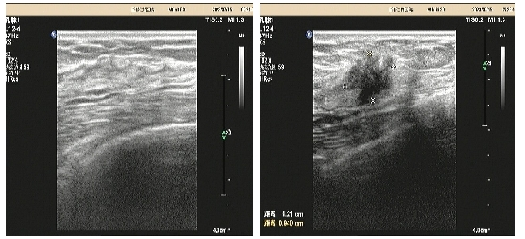

08、**女士,46岁

于2023年7月8日在邢台仁泰体检部体检,甲状腺彩超检查提示:甲状腺右叶可探及大小约0.9*0.7*0.7cm等回声结节,左叶可探及大小约0.8*0.7*0.8cm低回声结节,内可见多个点状强回声,边界清,形态欠规整,纵横比大于1。考虑:甲状腺结节伴钙化4b级。2023年7月8日首次回访,通知客户到三甲医院进一步检查。2023年7月14日跟踪回访,客户已在河北医科大学第二医院就诊,考虑甲状腺癌,准备手术治疗。